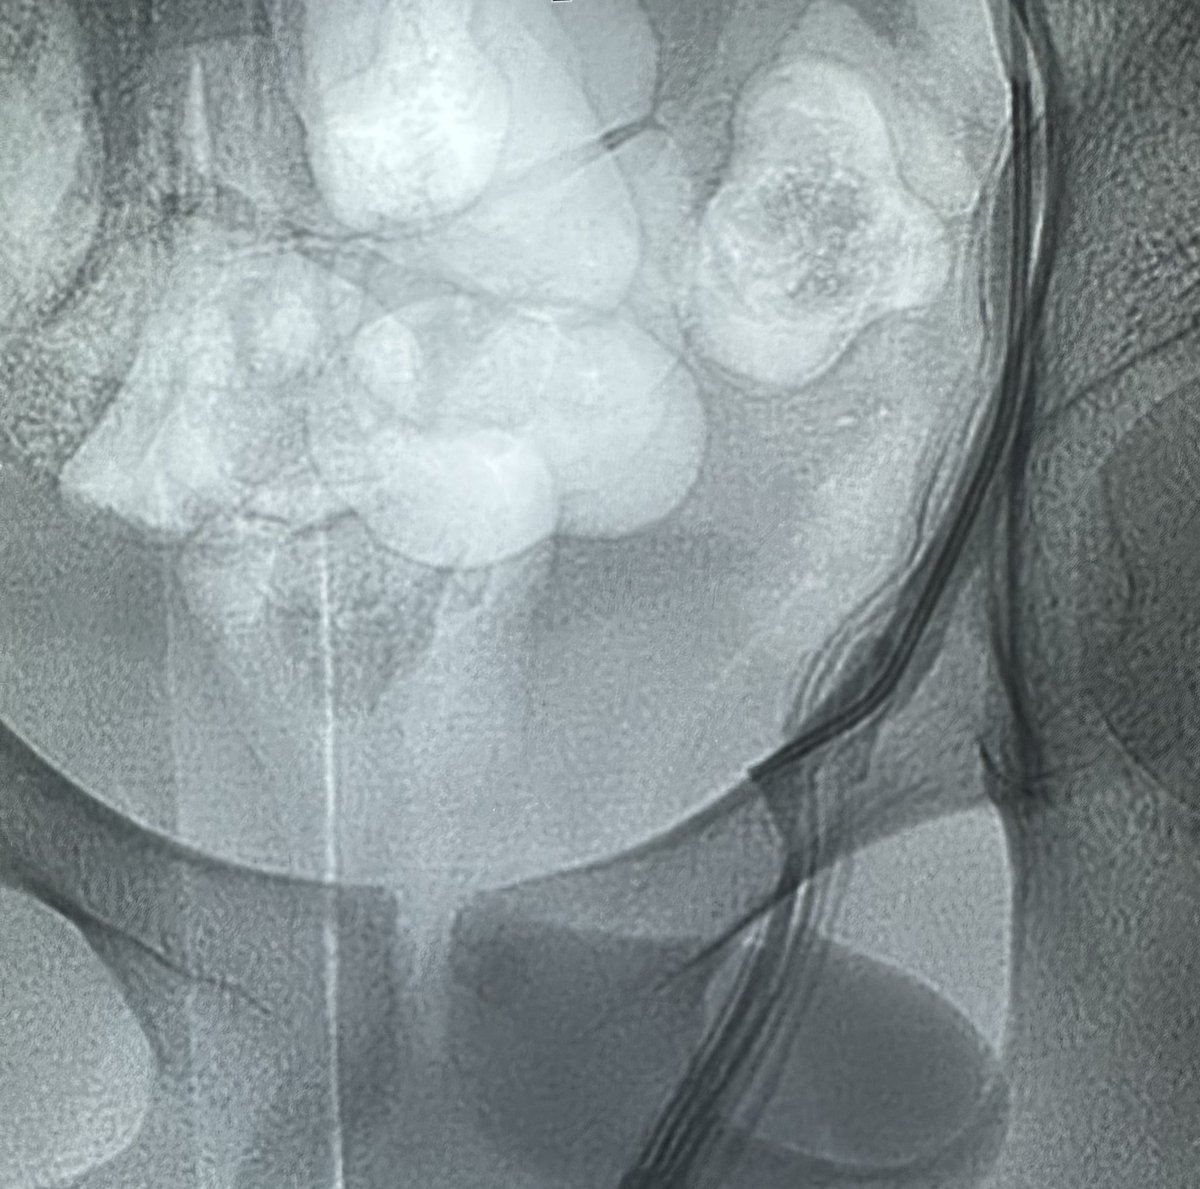

علاج دوالي الخصية بالأشعة التداخلية ، العلاج بالصمغ الطبي يعتبر أفضل وأحدث علاج. يتم إغلاق الدوالي والأوردة بدقة دون التعرض للشرايين والقنوات الليمفاوية الدقيقة. مثال لمريض لديه ما يفوق عن ٤٠ وريد ، لا يمكن ربطها جميعاً جراحياً. بالقسطرة؟ انتهينا من الجهتين خلال اقل من ١٠ دقائق.

طريقة تغلغل الصمغ الطبي في علاج الأوردة المغذية لدوالي الخصية بالقسطرة. اغلاق جميع الأوردة بدون المساس بالقنوات الليمفاوية (فلا يحصل قيلة مائية) ولا الشعيرات الشريانية الدقيقة (فلا يحصل ضمور) القسطرة والأشعة التداخلية اثبتت بالابحاث افضليتها على الجراحة من كل النواحي

من النوادر أن تكون دوالي الخصية اليمين أكبر من اليسار. بالقسطرة ، يمكن الكشف وعلاج الجهتين بسهولة عن طريق قسطرة واحدة باليد (فتحة لا تتجاوز ٢ مم) ويمكن علاج كل الدوالي حتى الصغيرة. ماذا عن الجراحة؟ يحتاج الجراح لعمل شق جراحي (٢-٣ سم) في كل جهة وفقط يمكنه ربط الدوالي الكبيرة…